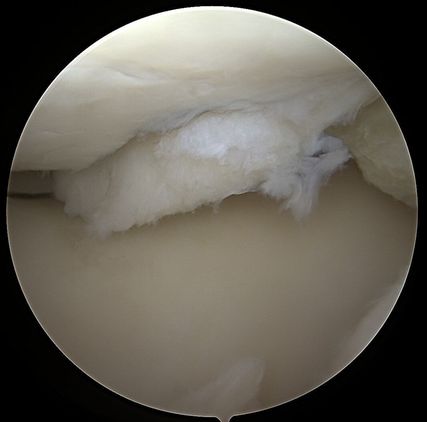

Abb. 1: Hypertrophie des Knorpelregeneratgewebes am lateralen Femurcondylus nach MACT (matrixgekoppelte autologe Knorpeltransplantation) mit subchondraler Zystenbildung

Abb. 2: Das arthroskopische Korrelat des MRT-Bildes zeigt ein instabiles Knorpelregenerat mit fehlender Integration und beginnender Delamination